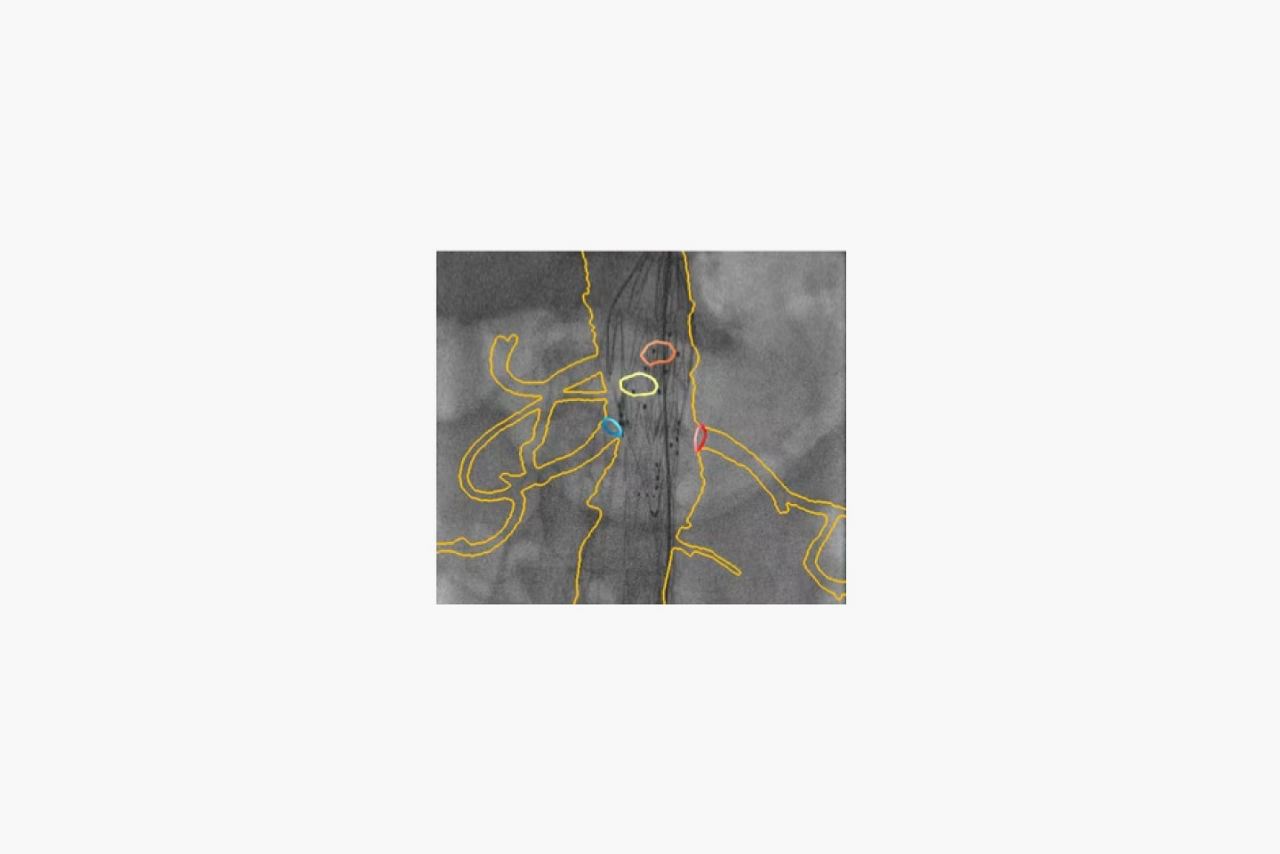

3D fusion imaging

Ensure placement with 3D visuals

3D fusion imaging

Ensure placement with 3D visuals